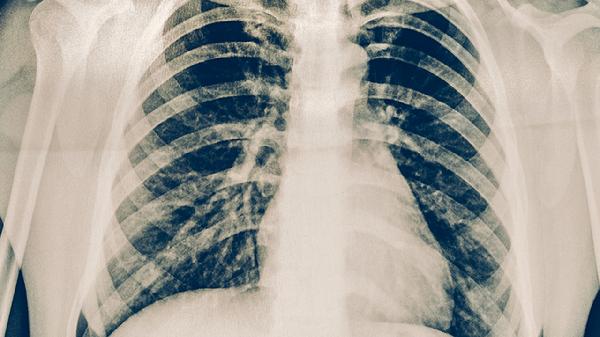

肺結(jié)核盜汗主要表現(xiàn)為夜間睡眠中大量出汗,常伴隨低熱、乏力等癥狀。盜汗可能與結(jié)核分枝桿菌感染引起的免疫反應(yīng)、體溫調(diào)節(jié)異常等因素有關(guān),需結(jié)合痰涂片、胸部影像學(xué)等檢查確診。

肺結(jié)核患者的盜汗通常具有規(guī)律性,多發(fā)生在后半夜或凌晨,出汗量可浸濕衣物或床單,且與環(huán)境溫度無關(guān)。這種盜汗往往持續(xù)數(shù)周以上,普通退熱治療無效。部分患者會同時出現(xiàn)午后潮熱、食欲下降、體重減輕等典型消耗性癥狀。結(jié)核菌產(chǎn)生的毒素作用于下丘腦體溫調(diào)節(jié)中樞,導(dǎo)致植物神經(jīng)功能紊亂是主要機制。病情進展期可能出現(xiàn)咳嗽、咯血等呼吸道癥狀。